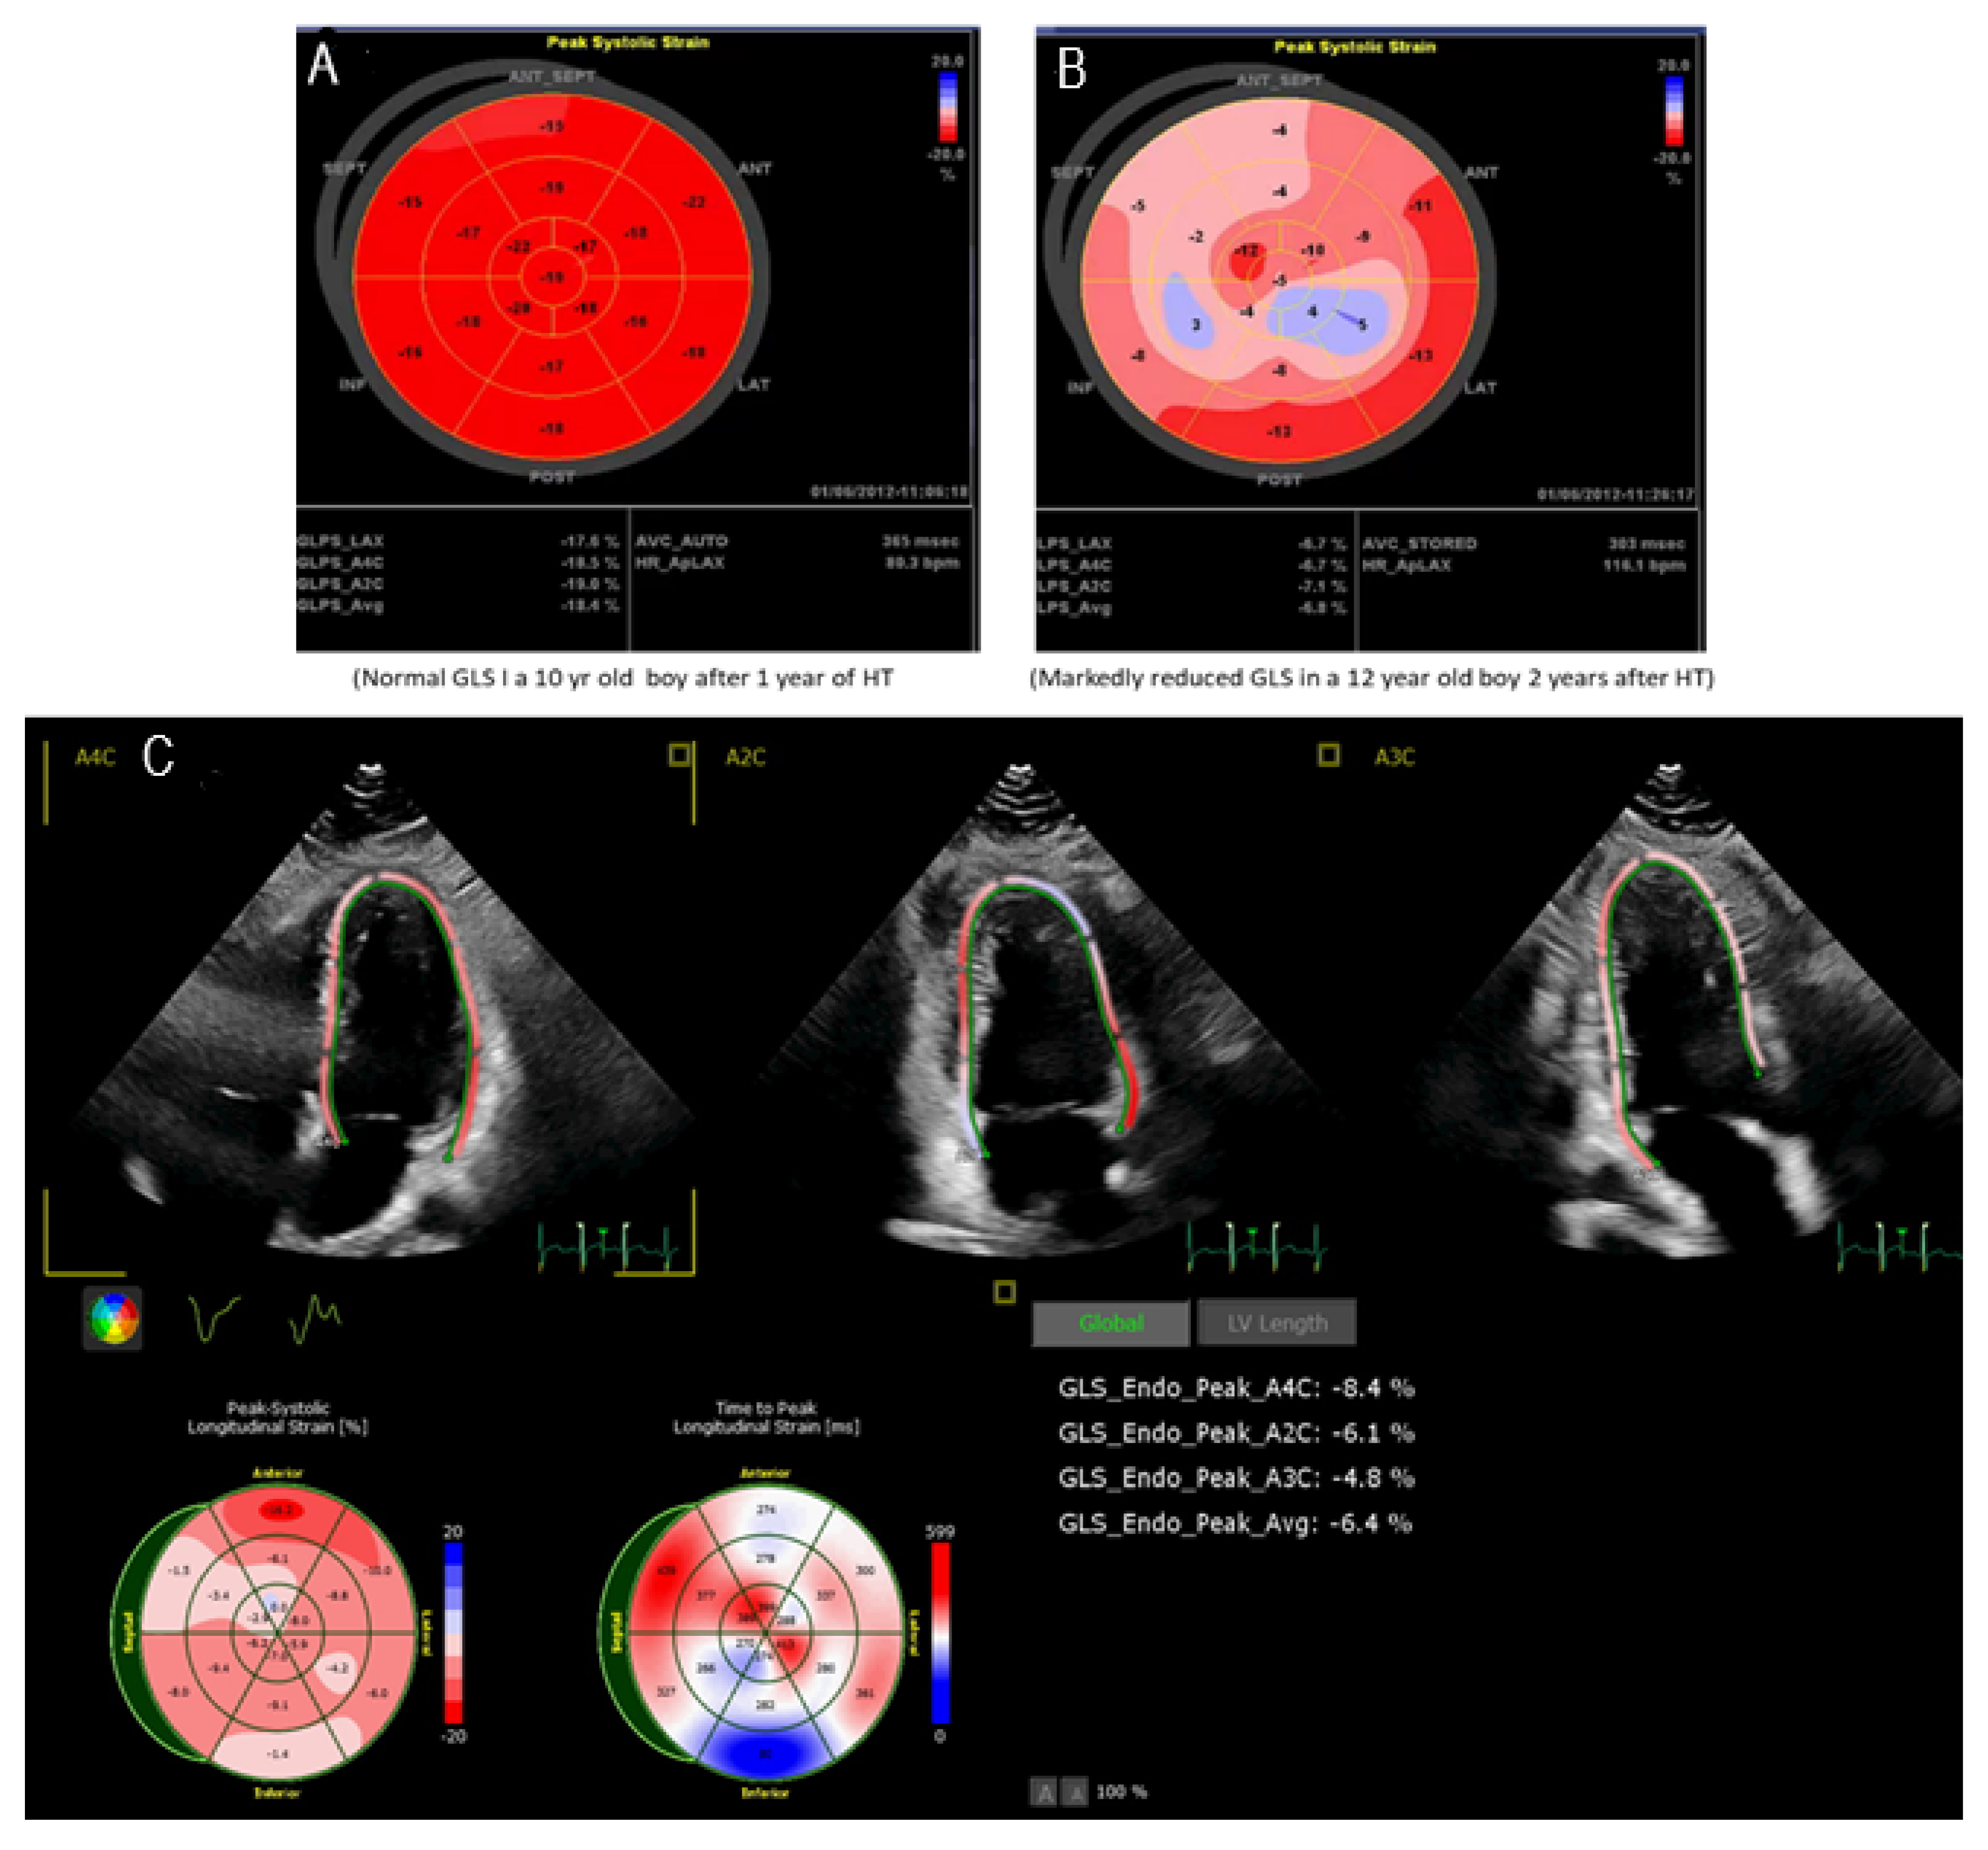

3.2. Speckle Tracking Echocardiography

- Wisotzkey, B.L.; Jorgensen, N.W.; Albers, E.L.; Kemna, M.S.; Boucek, R.J.; Kronmal, R.A.; Law, Y.M.; Bhat, A.H. Feasibility and interpretation of global longitudinal strain imaging in pediatric heart transplant recipients. Pediatr. Transpl. 2017, 21, 12909. [Google Scholar] [CrossRef]

- Buddhe, S.; Richmond, M.E.; Gilbreth, J.; Lai, W.W. Longitudinal Strain by Speckle Tracking Echocardiography in Pediatric Heart Transplant Recipients. Congenit. Heart Dis. 2015, 10, 362–370. [Google Scholar] [CrossRef] [PubMed]

- Boruta, R.J.; Miyamoto, S.D.; Younoszai, A.K.; Patel, S.S.; Landeck, B.F., 2nd. Worsening in Longitudinal Strain and Strain Rate Anticipates Development of Pediatric Transplant Coronary Artery Vasculopathy as Soon as One Year Following Transplant. Pediatr. Cardiol. 2018, 39, 129–139. [Google Scholar] [CrossRef] [PubMed]